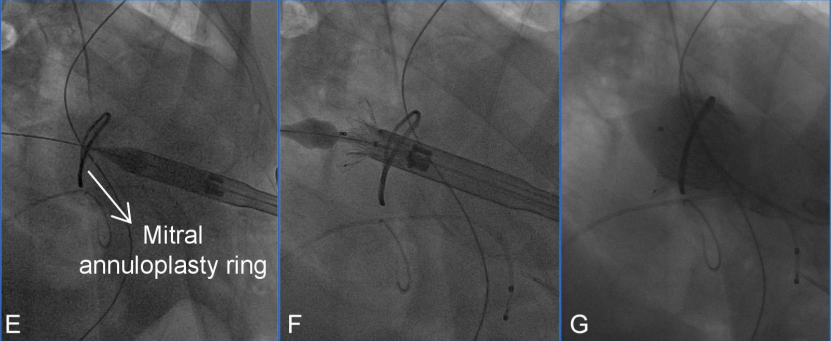

1.手术在全身麻醉及机械通气下进行,并在术中采用透视和TEE引导。首先在左前胸部行一4 cm小切口,经心尖建立穿刺通道。经右侧股动静脉分别穿刺置入6F鞘管,随后通过静脉鞘管将临时起搏电极导入右心室。同时,经右股动脉置入6F猪尾导管至左心室。

2.在成功建立标准心尖通道并使用六边形缝合方式固定穿刺口后,为了更清晰地显影左心室与左心房结构,术中调整至颅侧右前斜位角度进行操作。造影检查评估二尖瓣反流情况(图D)、左心室形态及瓣环结构。

图D:术中造影提示二尖瓣严重反流

4.随后,沿导丝将输送系统以逆行方式经心尖途径通过二尖瓣成形环推进至左心房。通过回撤输送系统的外鞘,释放出设计用于贴合D形二尖瓣瓣环的心房裙边,该裙边在TEE和造影的引导下精确覆盖于原瓣环及成形环之上,而瓣膜的心室部分仍部分保留在鞘管中。

5.在确认Mi-thos瓣膜的位置和对位无误后,缓慢回撤输送系统,使其准确定位于瓣环上。随后,140次/分快速起搏下释放心室部分的瓣膜,并通过其自带的固定倒钩装置牢固锚定于原生二尖瓣位置上。

6.术中左心室造影即刻显示Mi-thos生物瓣膜位置良好、形态理想,未见瓣内反流、瓣周漏(PVL)或左心室流出道梗阻(LVOTO)现象(新生左心室流出道面积为 374.6 cm²);TEE进一步评估瓣膜位置及功能,显示平均跨瓣压差为3 mmHg。